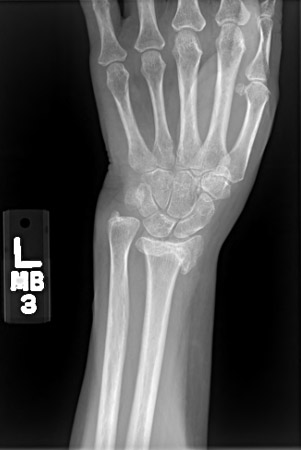

Fractures that are untreated, or those that are treated with non-operative methods with a loss of position, develop a malunion. Close radiographic follow-up of a non-operatively treated fracture is mandatory within the first 6 weeks to avoid a malunion. All malunions result in radiographic deformity. However, the cosmetic deformity may often be modest and functionally a malunion may not always require treatment. Patients with malunion and pain usually need treatment.[87][Figure caption and citation for the preceding image starts]: Posteroanterior x-ray showing malunion of the distal radius with significant shortening of the radius and relative lengthening of the ulna [Citation ends].